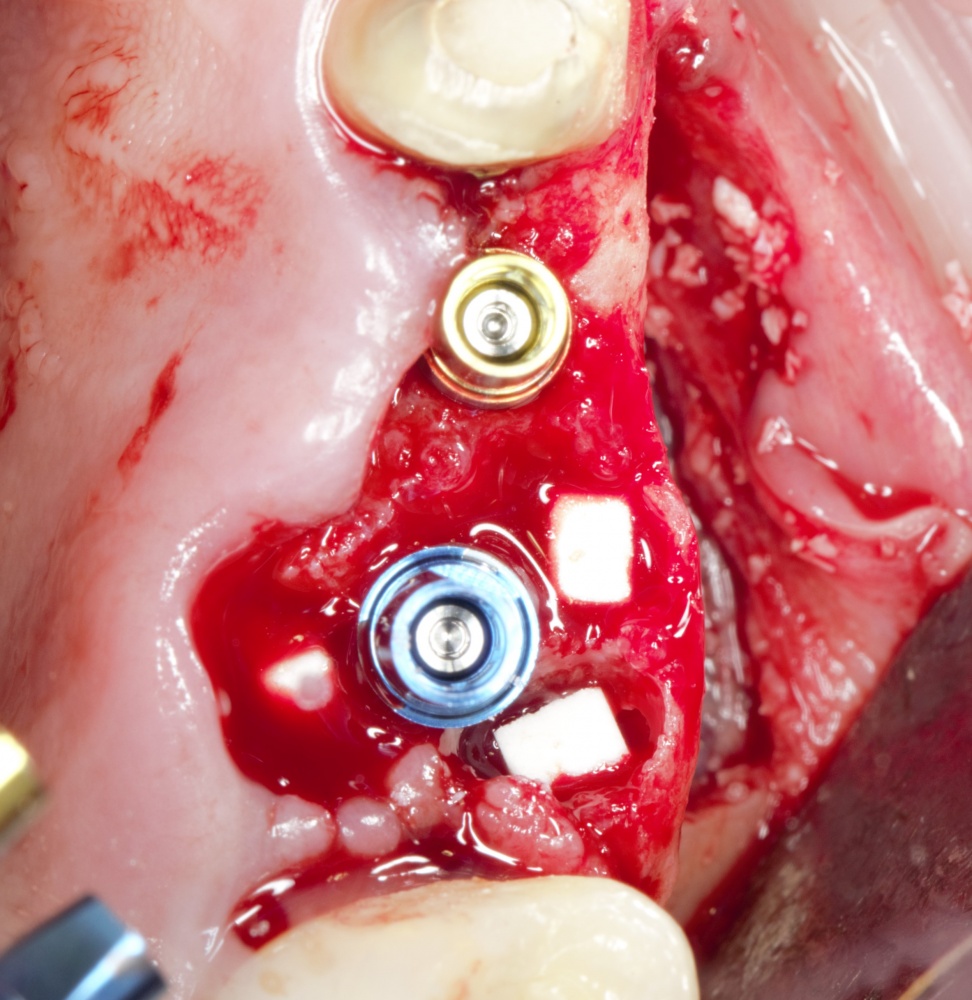

Простой синуслифтинг. Часть I.